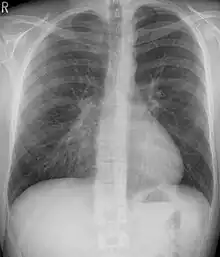

Many scales have been developed to determine the degree of deformity in the chest wall. Most of these are variants on the distance between the sternum and the spine. One such index is the Backer ratio which grades severity of deformity based on the ratio between the diameter of the vertebral body nearest to xiphosternal junction and the distance between the xiphosternal junction and the nearest vertebral body.[17] More recently the Haller index has been used based on CT scan measurements. An index over 3.25 is often defined as severe.[18] The Haller index is the ratio between the horizontal distance of the inside of the ribcage and the shortest distance between the vertebrae and sternum.[19]

Chest x-rays are also useful in the diagnosis. The chest x-ray in pectus excavatum can show an opacity in the right lung area that can be mistaken for an infiltrate (such as that seen with pneumonia).[20] Some studies also suggest that the Haller index can be calculated based on chest x-ray as opposed to CT scanning in individuals who have no limitation in their function.[21]